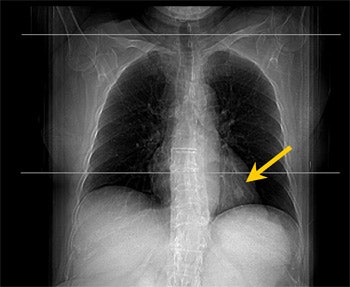

![]() |

| PET study from the same patient indicates very faint uptake activity that may be indicative of malignant process (SUV of 2.1). |